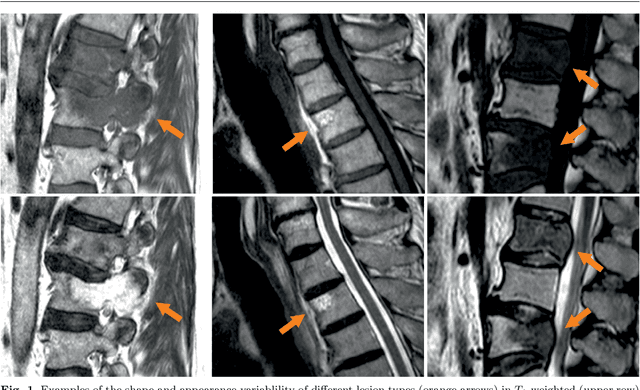

Abstract:This study's objective was to segment spinal metastases in diagnostic MR images using a deep learning-based approach. Segmentation of such lesions can present a pivotal step towards enhanced therapy planning and validation, as well as intervention support during minimally invasive and image-guided surgeries like radiofrequency ablations. For this purpose, we used a U-Net like architecture trained with 40 clinical cases including both, lytic and sclerotic lesion types and various MR sequences. Our proposed method was evaluated with regards to various factors influencing the segmentation quality, e.g. the used MR sequences and the input dimension. We quantitatively assessed our experiments using Dice coefficients, sensitivity and specificity rates. Compared to expertly annotated lesion segmentations, the experiments yielded promising results with average Dice scores up to 77.6% and mean sensitivity rates up to 78.9%. To our best knowledge, our proposed study is one of the first to tackle this particular issue, which limits direct comparability with related works. In respect to similar deep learning-based lesion segmentations, e.g. in liver MR images or spinal CT images, our experiments showed similar or in some respects superior segmentation quality. Overall, our automatic approach can provide almost expert-like segmentation accuracy in this challenging and ambitious task.